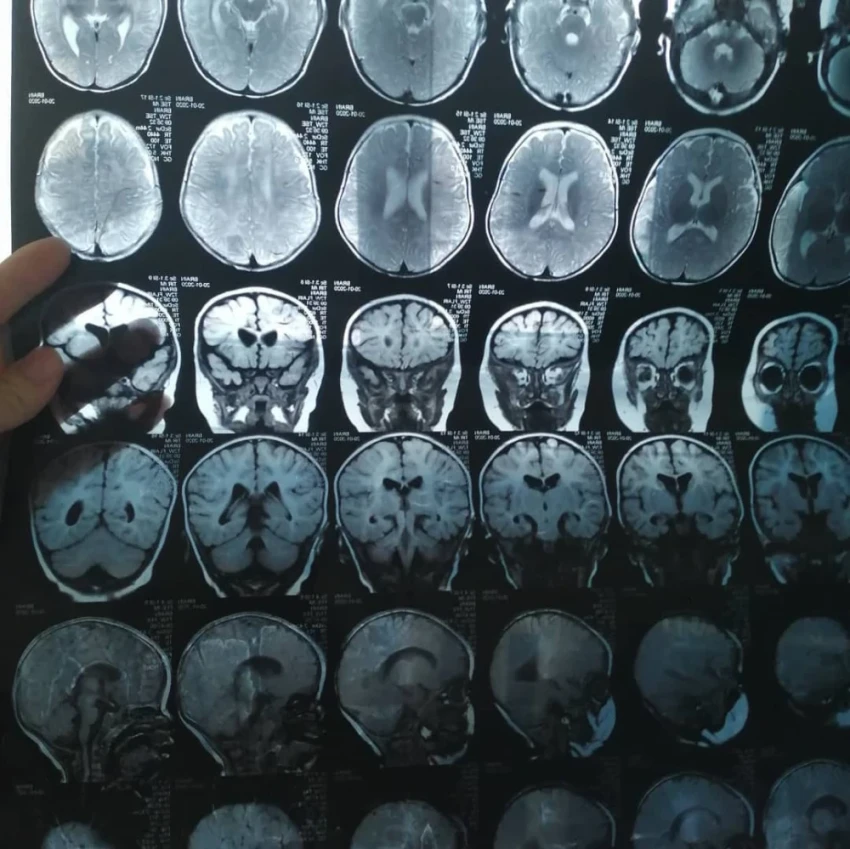

У дочери Бегимай ряд сложных диагнозов, ей нужна помощь.